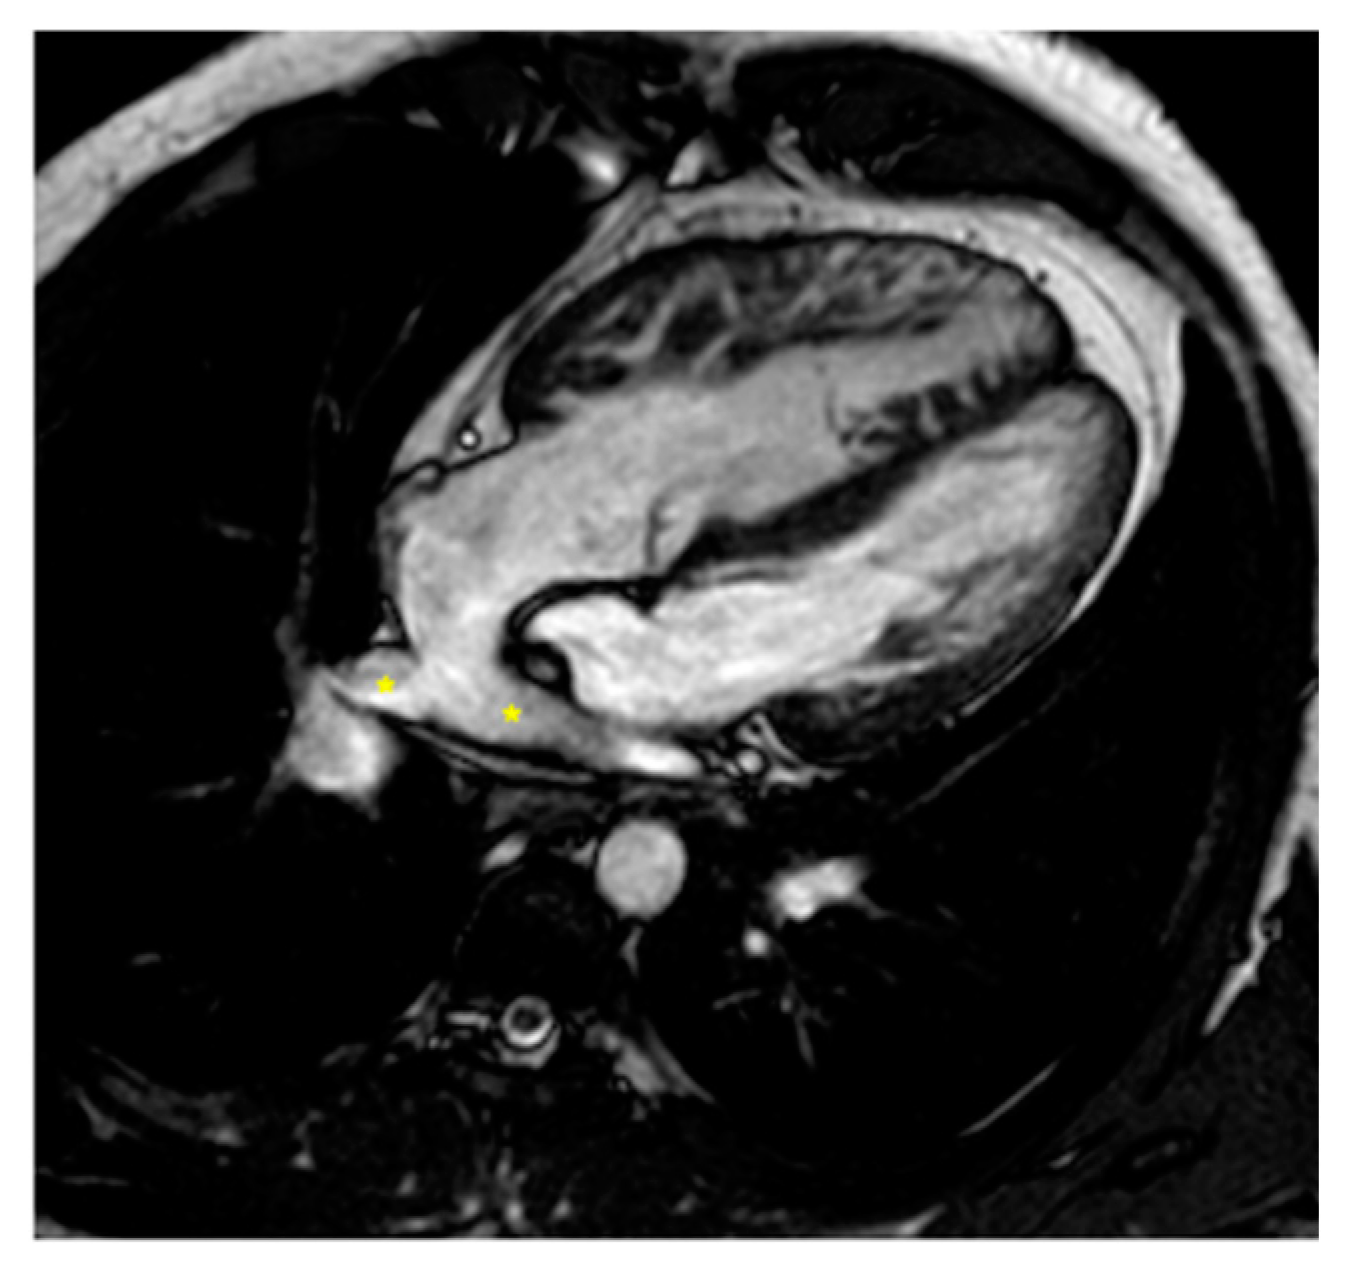

2.2.1. Dextro-Transposition of the Great Arteries (D-TGA)

Atrial Switch Operation and the Role of CMR Imaging